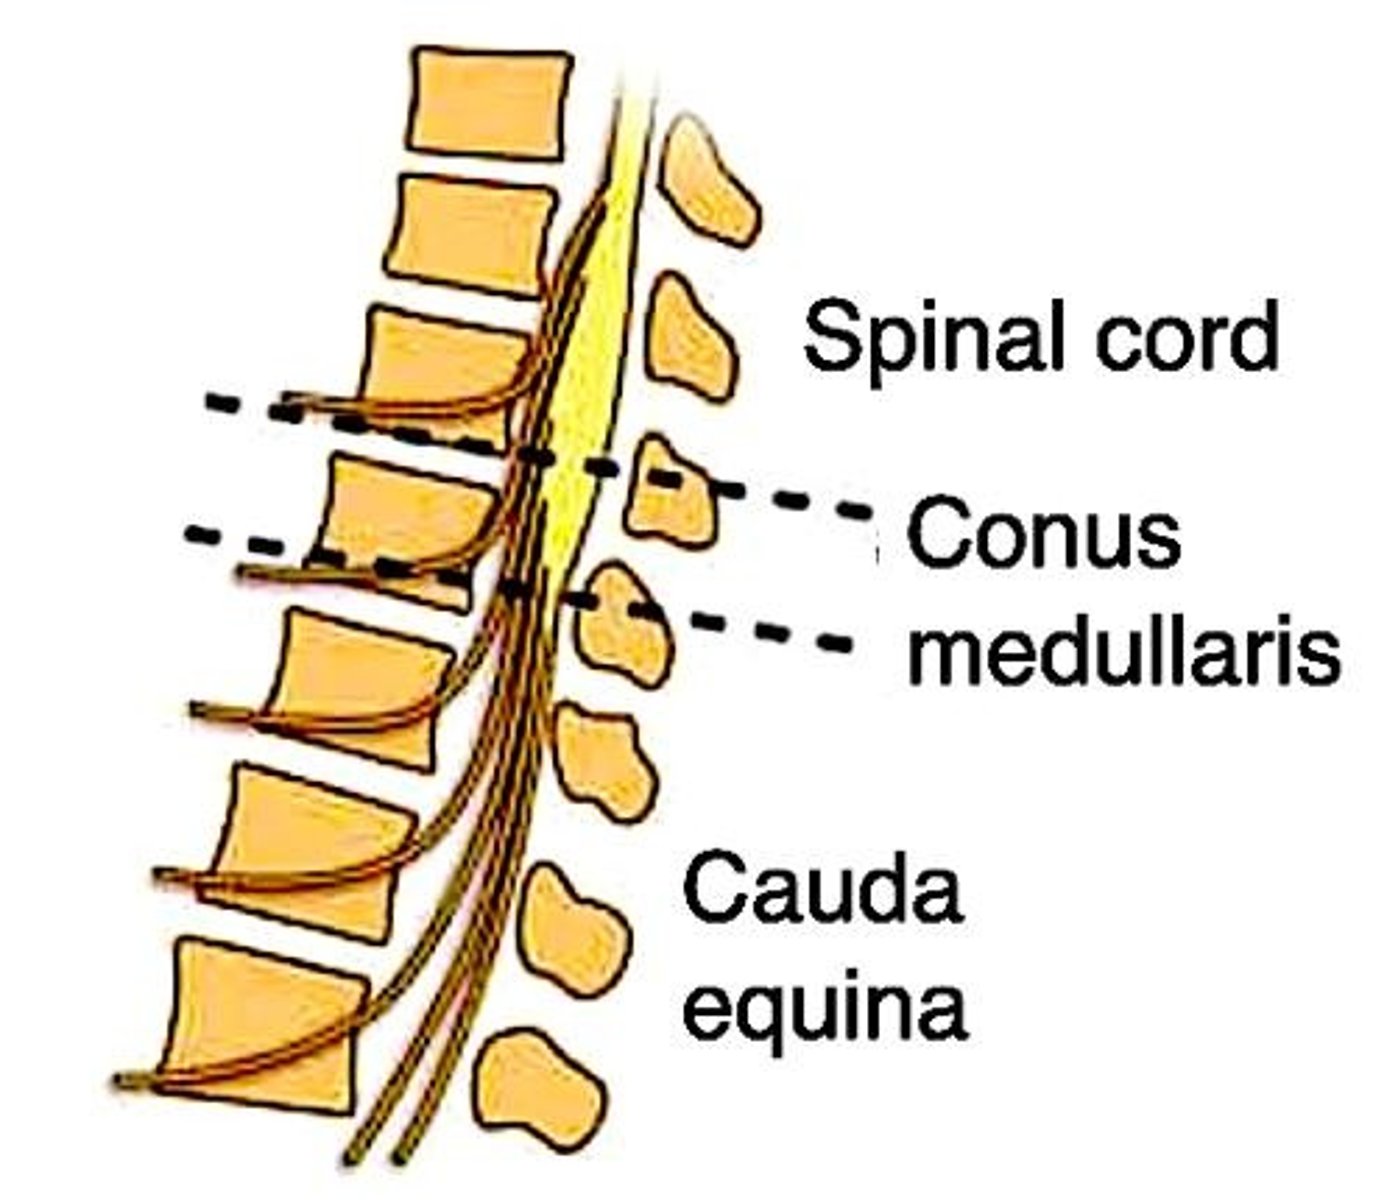

Spinothalamic tract

Pain and temperature sensation from contralateral body.

Decussation point

Cross-over (decussation) point is in spinal cord, meaning if, e.g., the left spinothalamic tract is damaged, we lose pain and temperature on the right side of the body below the lesion.

Corticospinal tract

Motor function from ipsilateral body.

Dorsal columns

Carry vibration + proprioception from ipsilateral body.

Syringomyelia

9/10 Qs will give bilateral loss of pain and temperature due to lesion of anterior white commissure (decussation point for spinothalamic tract).

Corticospinal Tract Involvement

Maybe 1/3 of Qs will also involve corticospinal tract, where you'll see some impaired motor function in addition to the bilateral loss of pain/temperature.

Impaired Motor Function

1/10 Qs will not mention pain/temperature loss but instead just give impaired motor function, where it sounds nothing like syringomyelia, but you're forced to eliminate to get there (on a 2CK Neuro CMS form).

Brown-Sequard Syndrome

Ipsilateral loss of vibration + proprioception (dorsal columns).

Brown-Sequard Syndrome

Ipsilateral loss of motor function (corticospinal tract).